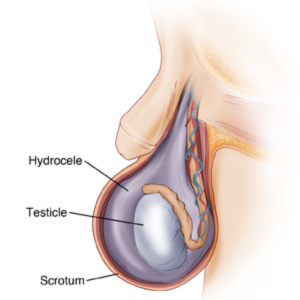

Hydrocele